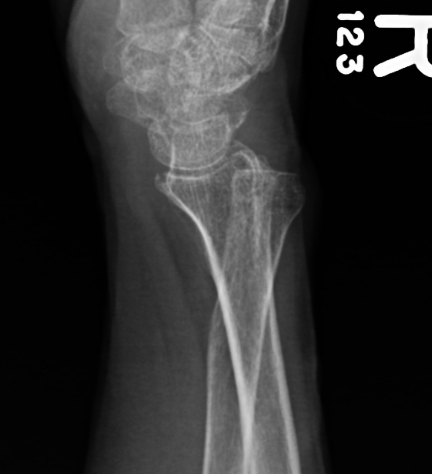

Isolated dorsal dislocation DRUJ

Isolated dorsal DRUJ instability with ulna sided TFCC tear

Xray

True lateral

- radial styloid overlies proximal scaphoid / lunate / triquetram

Dorsal subluxation of the distal ulna

CT